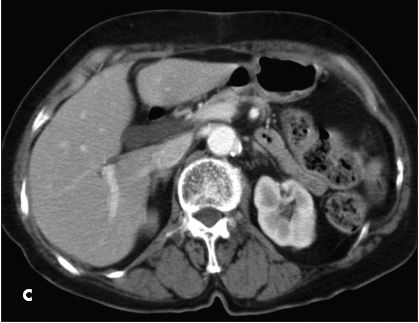

A 60-year-old woman with a 3-month history of worsening epigastric pain was referred for elective cholecystectomy after ultrasonography showed findings consistent with chronic cholecystitis. She had postprandial abdominal discomfort since age 4 years and had occasional nausea and vomiting but denied jaundice, change in bowel habits, or urinary symptoms.

This abdominal CT scan showed a dilated common hepatic duct confluence; the gallbladder was not visualized. Surgery revealed a large common bile duct at the level of the confluence between the right and left ducts at the hepatic hilum. A diagnosis of type II sphincter of Oddi dysfunction was entertained and an endoscopic sphincterotomy was performed.

Congenital agenesis of the gallbladder is a rare anomaly that results from failed development of the caudal portion of the original hepatic sacculation or lack of proper vacuolization of the gallbladder primordium. A female to male ratio of about 2 or 3 to 1 has been reported.

Affected adults usually are healthy and have no other congenital anomalies. However, common bile duct stones, carcinoma of the biliary tract, and primary sclerosing cholangitis have been associated with gallbladder agenesis. A familial or inherited trait has been described.